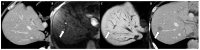

Gastric cancer (GC) is a common cancer worldwide. Its incidence and mortality vary depending on geographic area, with the highest rates in Asian countries, particularly in China, Japan, and South Korea. Accurate imaging staging has become crucial for the application of various treatment strategies, especially for curative treatments in early stages. Unfortunately, most GCs are still diagnosed at an advanced stage, with the peritoneum (61-80%), distant lymph nodes (44-50%), and liver (26-38%) as the most common metastatic locations. Metastatic disease is limited to the peritoneum in 58% of cases; in nonperitoneal distant metastases, the most involved GC metastasization site is the liver (82%). The eighth edition of the tumor-node-metastasis staging system is the most commonly used system for determining GC prognosis. Endoscopic ultrasonography, computed tomography, and 18-fluorideoxyglucose positron emission tomography are historically the most accurate imaging techniques for GC staging. However, studies have recently shown renewed interest in magnetic resonance imaging (MRI) as a useful tool in GC staging, especially for distant metastasis assessment. The technical improvement of diffusion-weighted imaging and the increasing use of hepatobiliary contrast agents have been shown to increase the diagnostic performance of MRI, particularly for detecting peritoneal and liver metastasis. However, no principal oncological guidelines have included the use of MRI as a first-line technique for distant metastasis evaluation during the GC staging process, such as the National Comprehensive Cancer Network Guidelines. This review analyzed the role of the principal imaging techniques in GC diagnosis and staging, focusing on the potential role of MRI, especially for assessing peritoneal and liver metastases.